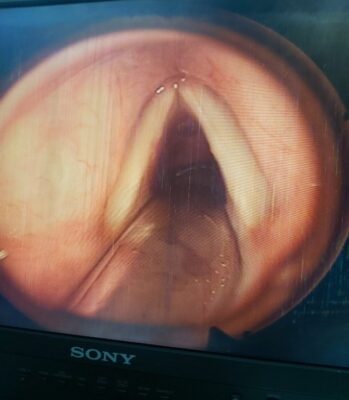

Hình ảnh :U nhú dây thanh (P)

1.1 Papiloma thanh quản (hay còn gọi là u nhú thanh quản) là một thương tổn lành tính ở thanh quản và khí quản. Bệnh u nhú thanh quản có thể gặp ở người lớn và trẻ em với diễn tiến lâm sàng có hơi khác nhau.

• Giải phẫu bệnh: Đại thể: là những khối sùi hình quả dâu tằm, hoặc hình súp-lơ nhiều nhánh màu trắng xám hoặc đỏ, rải rác hoặc tụ thành đám. Mỗi thành phần của đám sùi này gồm một trục mao mạch ở giữa bao quanh bởi mô liên kết. Tổ chức u nhú dễ chảy máu khi đụng vào, mềm, mủn do đó dễ tách ra và hít vào phổi khi ho hoặc hít sâu.

Vi thể: đây là một sự quá sản của biểu mô, mô liên kết và mạch máu. Sự phát triển này không bao giờ làm tổn thương lớp màng đáy. Sự khác nhau của u nhú thanh quản trẻ em và người lớn về mô học rất ít. Thường thì sừng hóa thấy nhiều ở người lớn, nhiều khi rất là diển hình, giống như mụn cóc ngoài da.